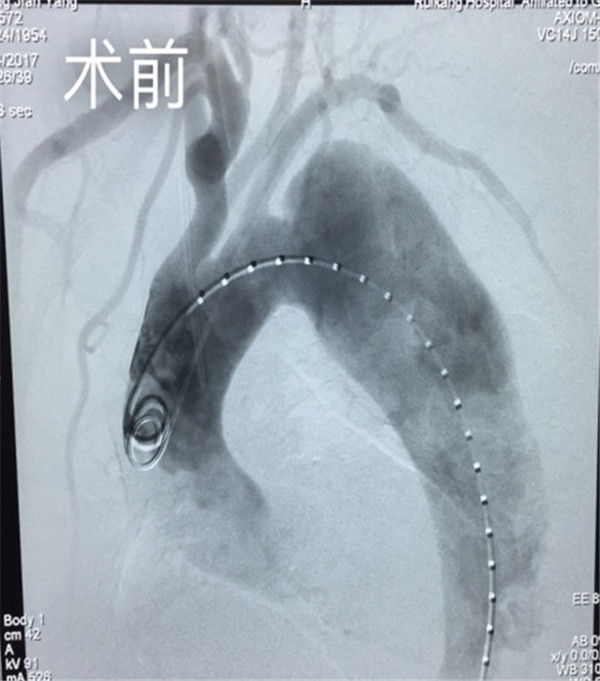

4月24日下午,经过1个多小时的手术,由张赋副主任及其团队完成了这一例ⅢA型主动脉夹层覆膜支架隔绝术。术后,经过半个月的院内观察,患者恢复良好,复查各项指标均达到正常标准,并康复出院。

主动脉夹层瘤是一种心血管系统的灾难性疾病,是当前最复杂、最危险的心血管疾病之一,是指血液通过主动脉内膜裂口进入主动脉壁并造成动脉壁的分离。若不及时进行有效治疗,死亡率极高,90%一年内死亡,且抢救非常困难。目前,Ⅲ型胸主动脉夹层、腹主动脉瘤的首选治疗方式是覆膜支架腔内隔绝术。覆膜支架植入是修复血管的一种新方式,与传统外科血管修补等方式相比,覆膜支架植入有更安全、简便、快捷、免开胸创伤小且疗效明确等优点。